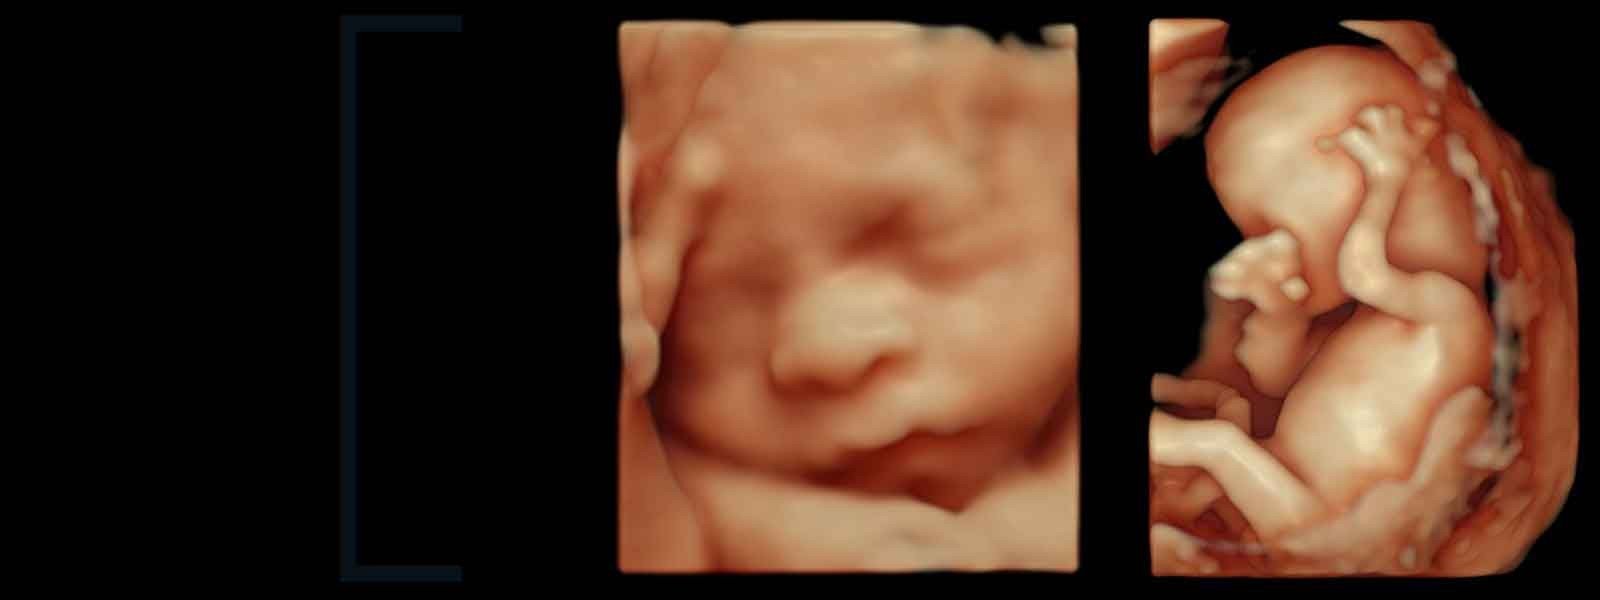

Somos un equipo de profesionales especialistas certificados en la mejor atención médica del paciente desde el asesoramiento y manejo reproductivo de la pareja; vigilancia del crecimiento y desarrollo del bebé dentro del útero por expertos en Diagnóstico Prenatal y Medicina Fetal; manejo del embarazo de alto riesgo, embarazo sin complicaciones y cuidado de la salud de la mujer en todas las edades, a través de los métodos más avanzados y sofisticados disponibles en la actualidad, para lograr los mejores resultados de salud en la mujer, madre y su niño.

Está integrado por un equipo de profesionales altamente calificados en el campo del diagnóstico especializado y tratamiento mínimamente invasivo, de notable experiencia y con la mejor formación en hospitales nacionales e internacionales de referencia, que trabajan en las distintas unidades clínicas de prestigio en nuestro medio. Expertos en diagnostico avanzado y tratamiento mínimamente invasivo (histeroscopia y ultrasonografía) con los últimos avances en los procesos de diagnóstico y tratamiento.

Ultrasonográfico y Análisis Clínico y Biología Molecular. Diagnóstico integral prenatal, neonatal, obstétrico, ginecológico y pediátrico así como también la patología general en hombre y mujeres.